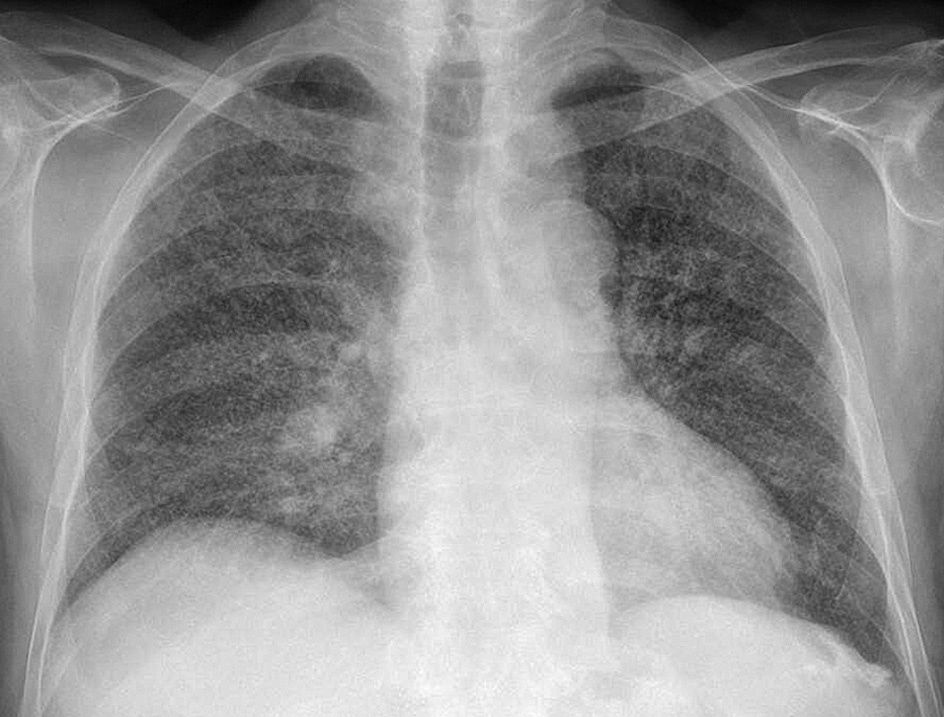

MANIFESTACIONES CLINICASNeumonia Tuberculosa: Primoinfección gralmente asintomatica o paucisintomatica Afecta fundamentalmente a lobulos medios o inferiores Se acompaña de adenopatias hiliares Forma de predominio en la infancia PLEURITIS TUBERCULOSA puede ser la manifestacion de una primoinfección Reactivación Tuberculosa Fundamentalmente segmentos apicales y posteriores de los lobulos superiores CAVITACIÓN Clinica insidiosa: Febricula, malestar general, pérdida de peso, sudoración nocturna, tos persistente y expectoración en ocasiones hemoptoica Dx baciloscopia

TUBERCULOSIS MILIAR O DISEMINADA Se produce por diseminación hematogena en personas con alteración grave del sistema inmune Mas fcte en ancianos Patognomonico tuberculos en la coroides, pero poco fcte Rx de torax Patrón micronodular tipico en grano de mijo